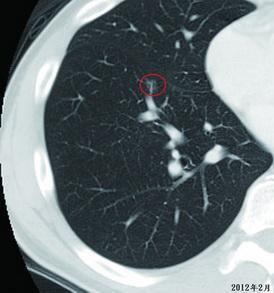

如果检查中肺结节有如下变化者,多考虑为良性:

1、短期内病灶外部特征变化明显,无分叶或出现极深度分叶,边缘变光整或模糊;密度均匀或变淡、在密度未增加的情况下病灶缩小或消失

3、实性结节2年以上仍稳定,但这一特征并不适用于磨玻璃样结节,因原位腺癌和微浸润腺癌阶段的磨玻璃结节可长期稳定。

这里的长期指超过2年或更长时间,但实性结节究竟稳定多长时间提示为良性,目前尚未明确。